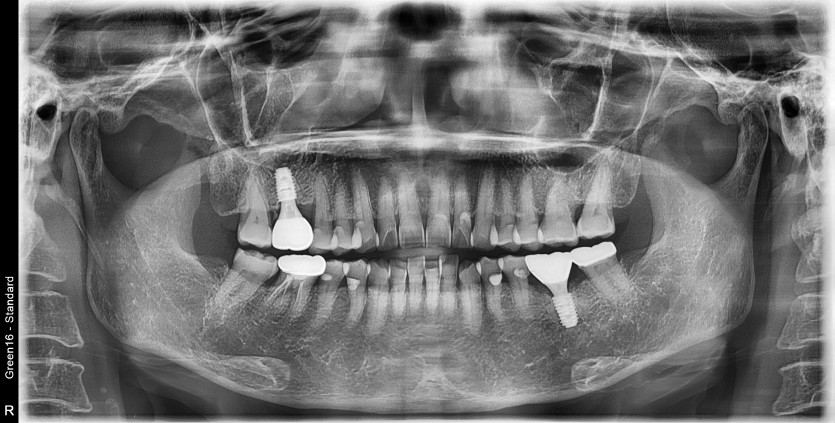

#36 타병원 임플란트 뼈이식 + 재식립